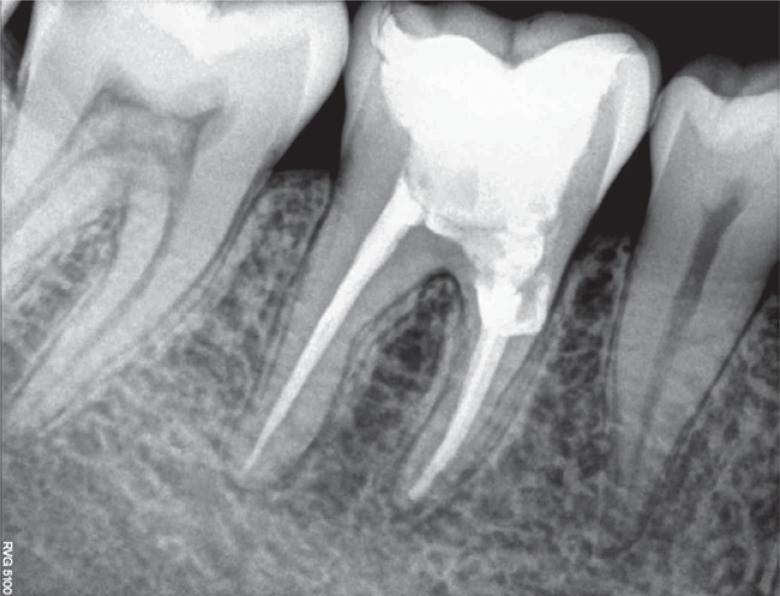

Figure 5Post-obturation radiograph.

Based on the clinical and radiographic findings, a treatment plan was made. Endodontic therapy was initiated (

Figure 3). Following the cleaning and shaping of the canals, calcium hydroxide (Avue Cal, Dental Avenue, Param Enterprises, Pune, India) was placed as an intracanal medicament for one and half months. The dressing was changed every two weeks. Once the tooth demonstrated signs of radiographic healing of the periapical lesion and the absence of symptoms, the obturation was completed with cold lateral condensation and resin-based sealer (AH Plus, Dentsply DeTrey, Konstanz, Germany,

Figures 4 and

5) and the tooth was temporised. Since the remaining amount of dentin around the mesial orifice and on the floor of the chamber was compromised and nearly approached the furcation, we decided to place Biodentine (Septodont, Saint-Maur-des-Fossés, France) as a dentin substitute base. The following day, a 2 mm thick layer of Biodentine was placed on the floor and around the mesial orifice (

Figure 6).